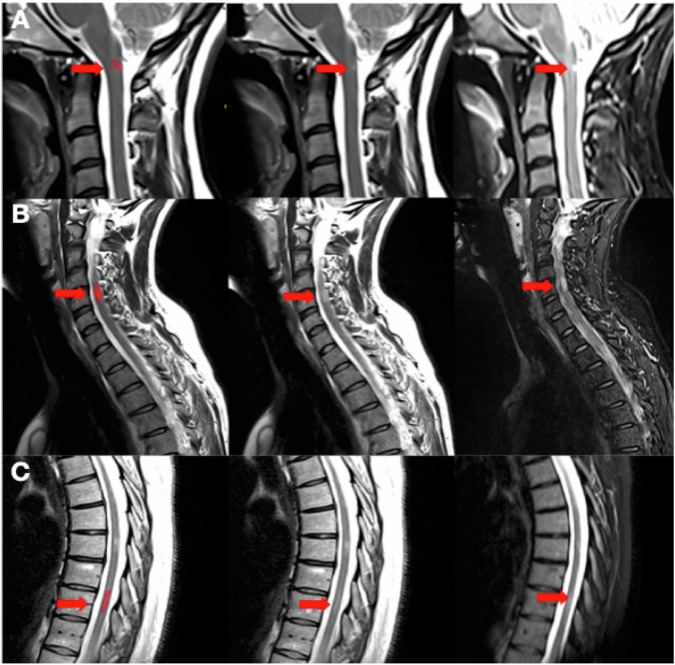

Materials and methods: A DL tool was developed based on SC sagittal T2 and STIR acquisitions from the imaging database of the French MS registry (OFSEP), including retrospective data from 40 different scanners. A multi-reader study based on retrospective data was performed between December 2023 and June 2024 to compare the performance of 20 clinicians in interpreting upper and lower SC acquisitions with and without the use of the tool. A ground truth was established by three experts. Sensitivity, precision, and inter-reader variability were evaluated.

Results: We included 50 patients (39 females, median age: 41 years [range: 15-67]) with SC MRI acquired between February 2017 and December 2022. When reading with the tool, the clinicians' mean sensitivity to detect SC lesions improved (from 74.3% [95% CI = 67.8-80.6%] to 79.2% [95% CI: 73.5-85.0%]; p < 0.0001), with no evidence of difference in the mean precision: (69.0% [95% CI: 62.8-75.2%] vs 70.1% [95% CI: 64.3-75.9%]; p = 0.08). Inter-reader variability in lesion detection was slightly improved with the tool (Light's kappa = 0.55 vs 0.60), but without statistical difference (p = 0.056).